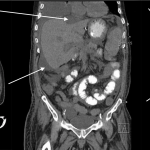

ABDOMINAL/PELVIC CT-SCAN WITH ONLY IV CONTRAST

Key features of ascites seen in this imaging modality are:

- Density similar to water (transudative ascites): typically between -10 and + 10 HU

- Density slightly above water (exudative ascites): can be above 15 HU

- Does not enhance with IV contrast: typically this should not occur, however delayed enhancement of ascites can occur in some cases. Perfused organs should appear significantly brighter then surrounding ascites.

The gallery below organizes examples of how ascites will appear on a abdominal/pelvic CT-scan with the usage of only IV contrast. Click on the thumbnails below to open up the gallery: